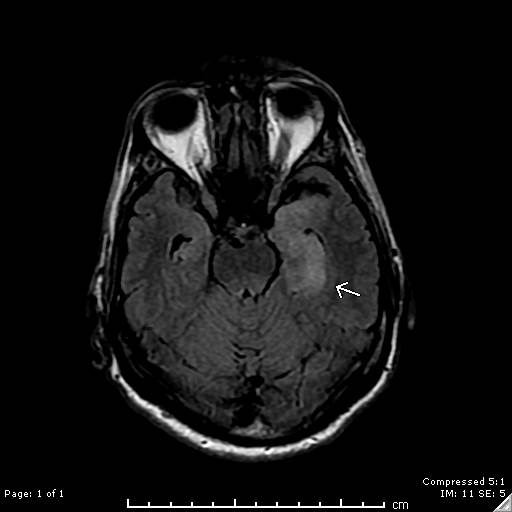

Case Presentation: A 59-year-old male was transported to the emergency department by concerned family and friends who had noted progressive confusion over a 72-hour period. The patient had failed to perform several routine parenting and household duties, and was unable to recognize familiar friends and colleagues. The patient denied fever, headache, and neck discomfort. There was no reported history of alcohol or substance abuse. He denied any at risk behaviors for HIV. Neurological exam was remarkable only for subtle cognitive defects. CAT of the brain was unremarkable. Brain MRI revealed asymmetric edema in the left mesial temporal lobe with restricted diffusion along the hippocampal cortex, suggestive of viral encephalitis (Image 1). Lumbar puncture was performed and demonstrated pleocytosis with CSF RBC of 3,000/uL, and WBC 16/uL with 79% lymphocytes. CSF protein was elevated at 65 mg/dL. Acyclovir was empirically started for presumed herpes encephalitis. Subsequently, HSV Types 1 and 2 PCR testing on the CSF returned as negative, and serum testing for HIV1 antibody returned as positive. HIV1 RNA by PCR was 68,800 copies/mL. Absolute CD4 count was 121/uL. Serum RPR was as positive at 1:128, and reflex antibody testing for Treponema pallidum was positive. CSF VDRL was also positive at 1:4. Treatment with a planned two-week course of ceftriaxone was initiated. The patient will begin anti-viral therapy for HIV as an outpatient.

Discussion: Neurosyphilis is defined as infection of the central nervous system by Treponema pallidum, a spirochete that is transmitted sexually. It is most common in patients infected with HIV. A positive CSF VDRL at any dilution establishes a definitive diagnosis. Described by Sir William Osler as “The Great Imitator”, syphilis can present with a myriad of different clinical manifestations. Less than ten cases of neurosyphilis with signs, symptoms, and imaging findings consistent with herpes simplex encephalitis (PLEDS and hyperintense T2-weighted signals involving the temporal lobe) have been reported in the world literature. Other entities that may rarely present with similar clinical and MRI findings include systemic lupus erythematosus related vasculitis, gliomatosis cerebri, acute hemorrhagic leukoencephalitis, prolonged partial complex seizures, and paraneoplastic limbic encephalopathy. Treatment of choice of neurosyphilis is a prolonged course of intravenous penicillin, with repeat CSF exam at 3 months to assess clearing of pleocytosis and lack of VDRL reactivity.